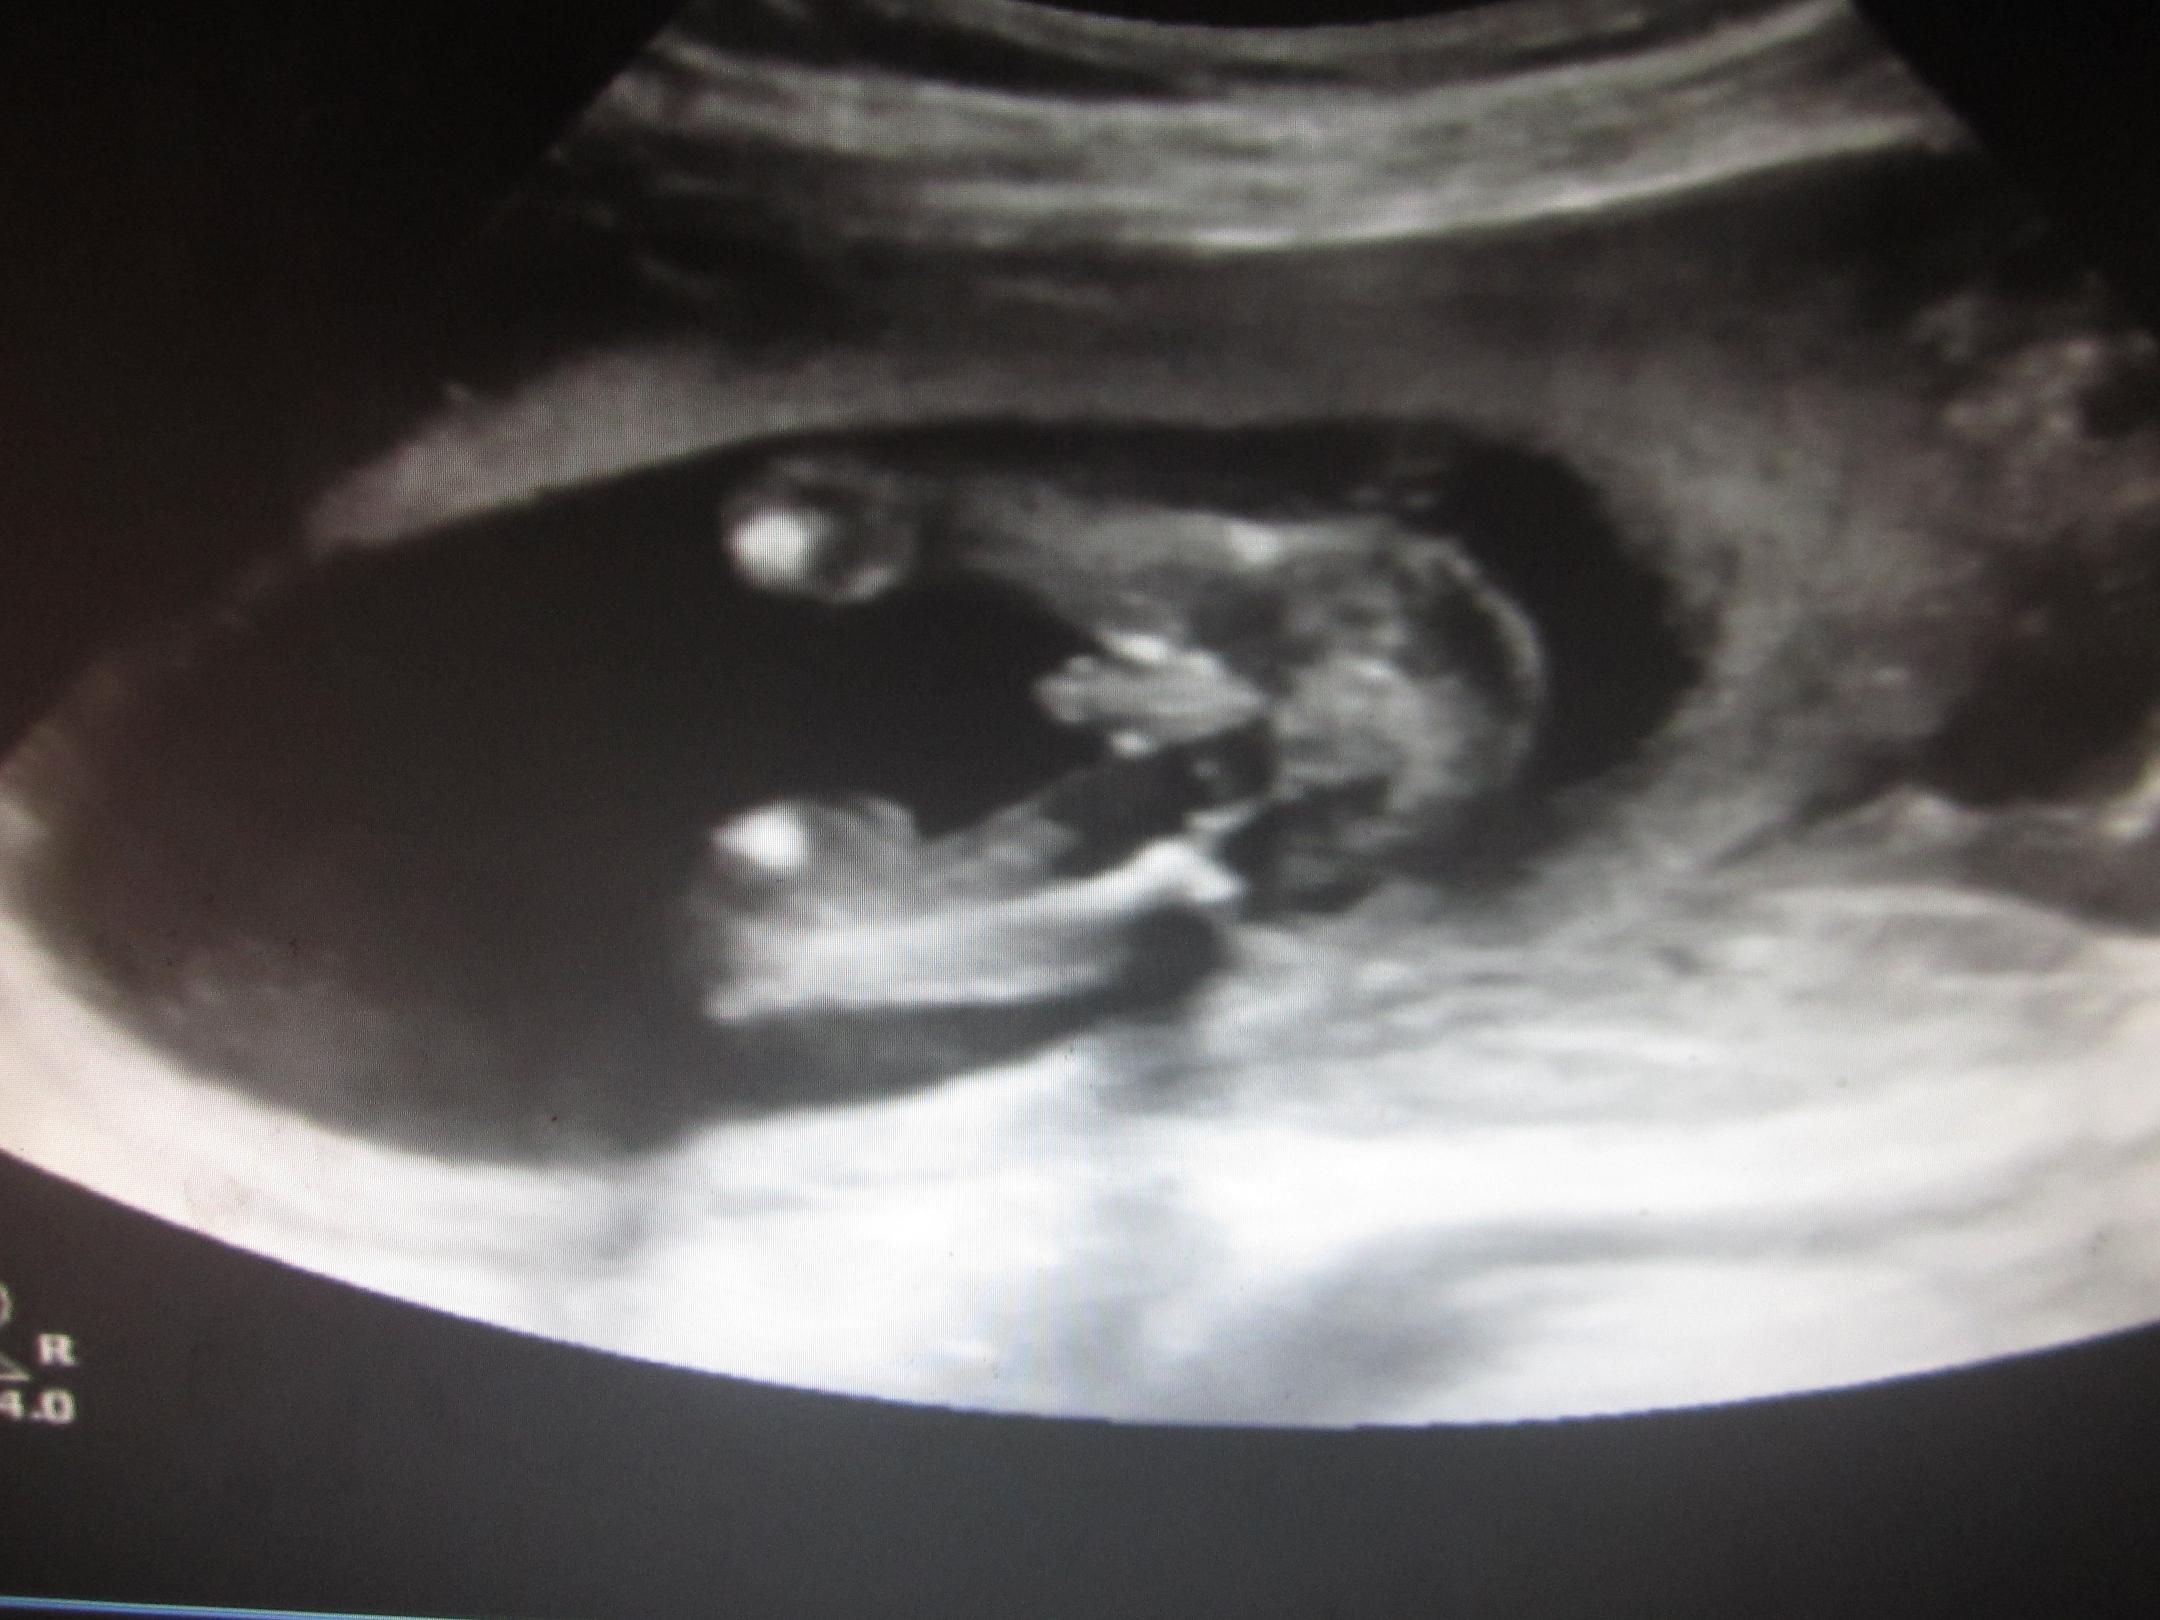

Attachment 6900

And the potty shot, he is definatly not shy :)

Well, that has to be the BEST potty shot in the history of boy potty shots on the web! No doubt and clear as can be.